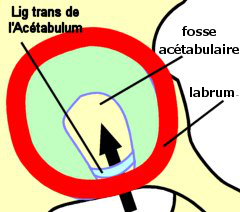

- En DD : sur la face externe de l'os coxal, dans son segment moyen,

l'échancrure ischio-pubienne en BAS. Elle présente 2 régions : à la

antérieure et postérieure) et au centre, la fosse acétabulaire

-

(le labrum). C'est un fibro-cartilage enroulé à la périphérie

cartilage qui répond à la tête fémorale). Au niveau de l'échancrure

acétabulaire de la cavité articulaire).